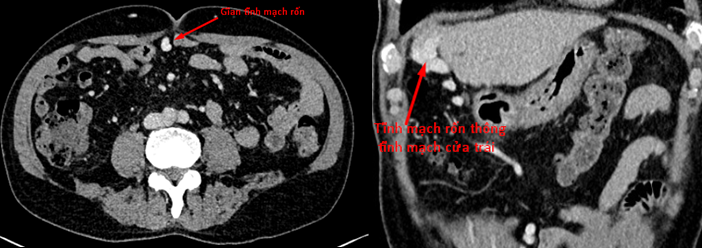

Với những trường hợp bệnh nhân có gan quá xơ, tiếp cận khó khăn bằng kim Agiocath và tiềm ẩn nguy cơ không đóng kín được đường vào sau khi kết thúc can thiệp gây tràn máu ổ bụng, nguy hiểm cho bệnh nhân. Hoặc tĩnh mạch cửa giảm chức năng, teo nhỏ hoặc có huyết khối, việc tiếp cận qua tĩnh mạch cửa là bất khả thi. Trên những trường hợp đó nếu bệnh nhân tồn tại tuần hoàn bàng hệ cửa chủ, mà nhánh đó dễ dàng tiếp cận điển hình là TM rốn, chúng ta có thể tiến hành can thiệp xuôi dòng qua TM rốn.

Hình 2: Bệnh nhân có giãn TM rốn thông với TM cửa trái trên phim chụp MSCT